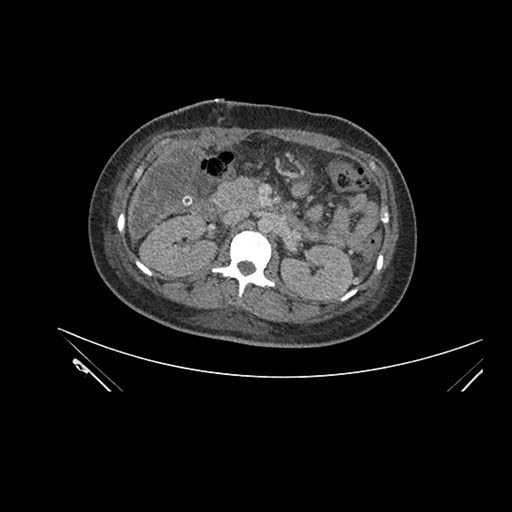

Axial Arterial

Imaging analysis

Based on initial findings, which issue(s) would you be most concerned about?